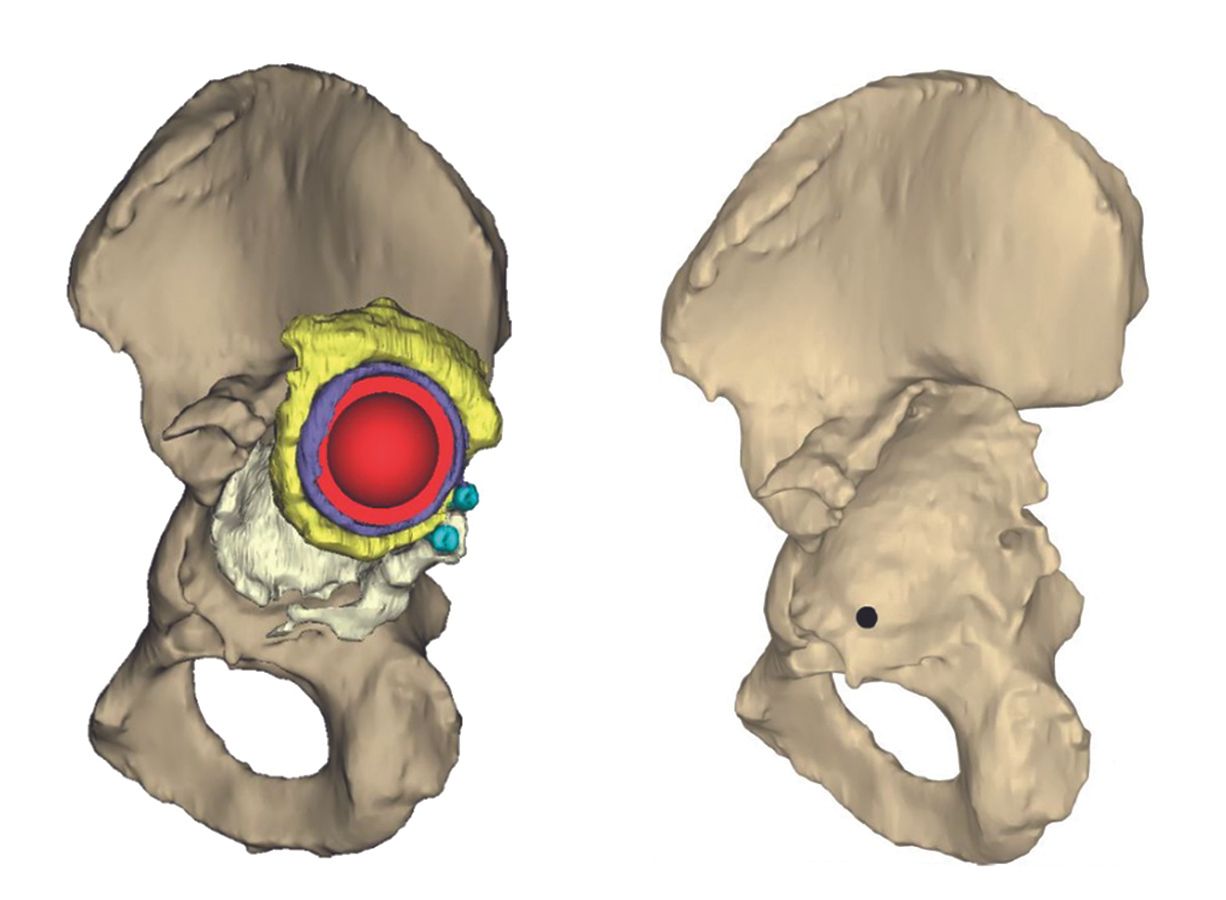

One of the latest instruments in the orthopedic surgeon’s armamentarium to face these challenges is a patient matched revision system (aMace, Materialise, Leuven, Belgium). This system consists of a 3D-printed monobloc trabecular titanium implant with integrated flanges, augments, cup and holes to guide screw placement (figure 1).

A CT scan of the complete pelvis is uploaded to an online platform. Special software is used to subtract all parts of the pre-existing reconstruction (e.g. previous implant, screws, cement, mesh). This allows to assess the ultimate bone defect according to the Paprosky classification (figure 2).

Additionally, bone quality is assessed by Hounsfield units and presented with a colour gradient from red (inferior) to green (superior) (figure 3).

By taking into account the bone quality the defect matched acetabular implant is designed restoring the centre of rotation, augmenting the defects and providing optimal screw orientation (figure 4).